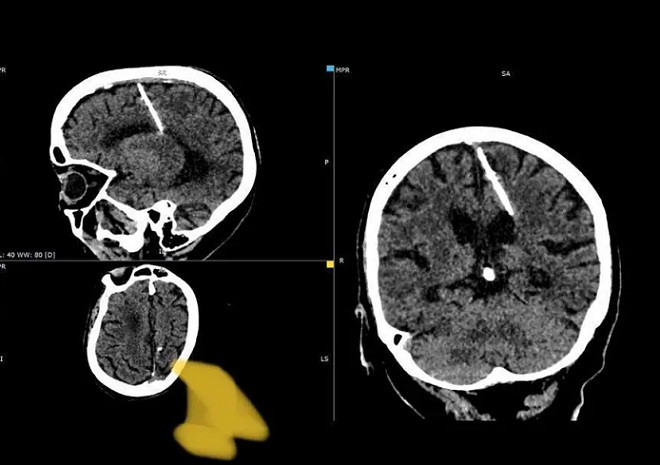

Cũng theo Sở Y tế Sakhalin, trong trường hợp này, cây kim dài gần 3cm đã đâm vào thùy đỉnh trái, nhưng không tạo ra tác dụng như mong muốn. Bà lão đã chung sống với cây kim mà không hề hay biết trong suốt 80 năm qua. Bà cũng chưa từng phàn nàn về việc bị đau đầu.

Mọi chuyện chỉ được phát hiện, khi bà lão đi khám và chụp CT. Các bác sĩ quyết định sẽ không rút cây kim vì lo sợ nó có thể gây ảnh hướng xấu tới bệnh nhân.